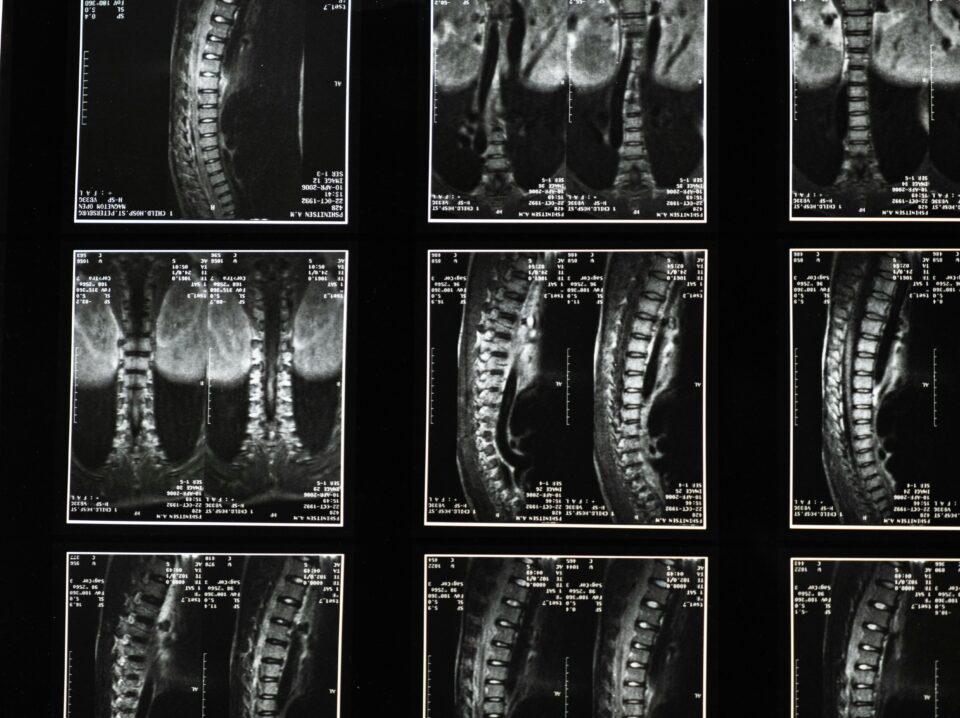

Healthcare

Medical Imaging

Streamlining MRI Analysis with Privacy-Compliant DICOM Processing